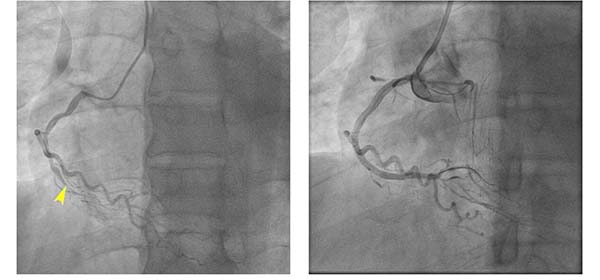

2025年的收官病例,是一位来自东北的39岁年轻患者,因严重冠心病合并心力衰竭辗转多家三甲医院求治未果,最终慕名来到北京朝阳医院心内科。入院次日行冠状动脉造影显示三支冠状动脉完全闭塞,面对极高风险,心内科主任赵林审慎评估、迎难而上,决定优先开通有优势的右冠状动脉。在主任医师张涛、副主任医师付源的通力协作下,仅用30分钟便成功开通闭塞血管,使尘封已久的右心室心肌重新焕发生机,也为北京朝阳医院心脏中心2025年的介入手术画上了圆满而有力的句号。

患者术前(左图)与血管开通后(右图)对比